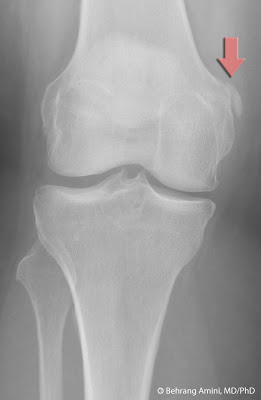

Pellergrini-Stieda Disease